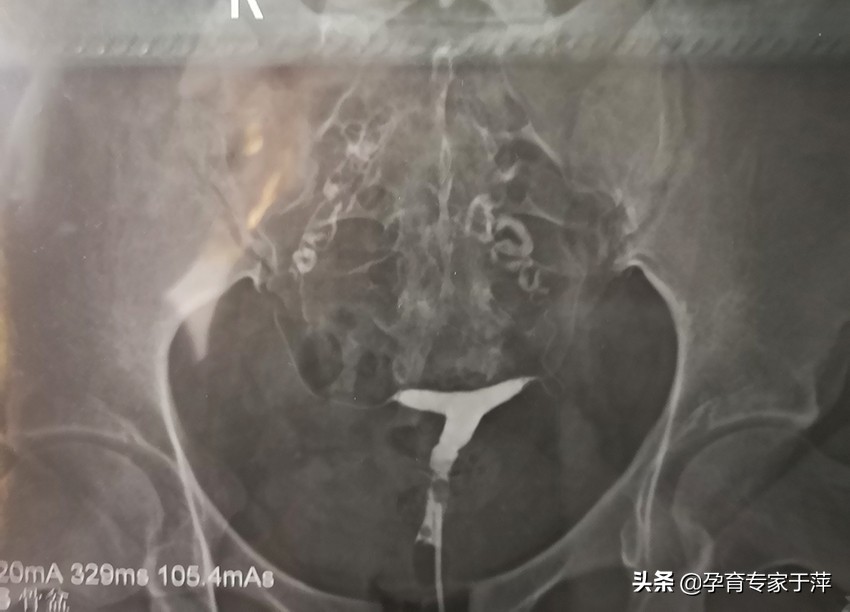

4、输卵管上举

盆腔炎症可以导致输卵管黏连上举,会造成输卵管输送能力下降,不易受孕,或容易造成宫外孕。